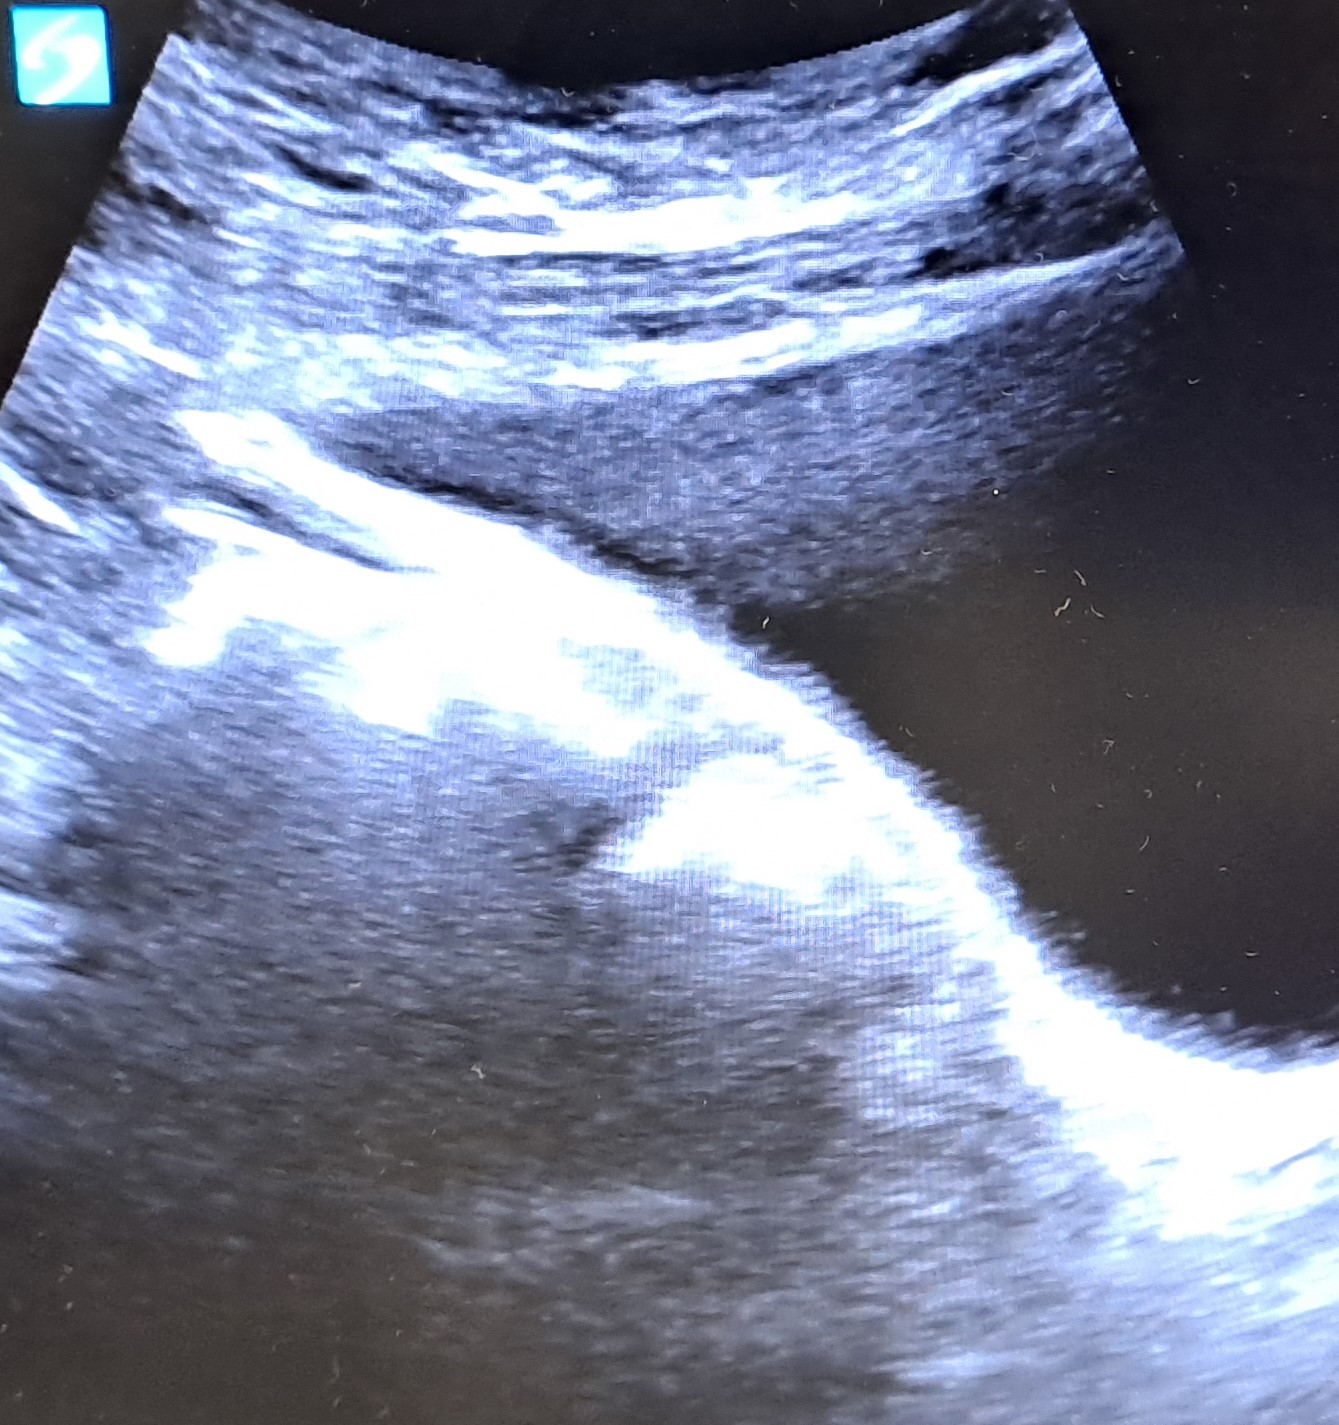

Realizamos ecografía clínica objetivando vejiga replecionada objetivando material isoecogénico en región posterior de la vejiga con 3 líneas hiperecogénicas con sombra acústica posterior.

Dada la objetivación de cuerpo extraño en ampolla rectal se decidió vigilar deposiciones.

En este caso la ecografía clínica ha sido útil para valorar la presencia de un cuerpo extraño en el tubo digestivo, dado que en la radiografía realizada en Atención Primaria no se objetivaba el cuerpo extraño al no visualizarse la ampolla rectal. Así fue posible gracias a la ecografía clínica objetivar el cuerpo extraño y no repetir la radiografía ahorrando radiación y desplazamientos del paciente.